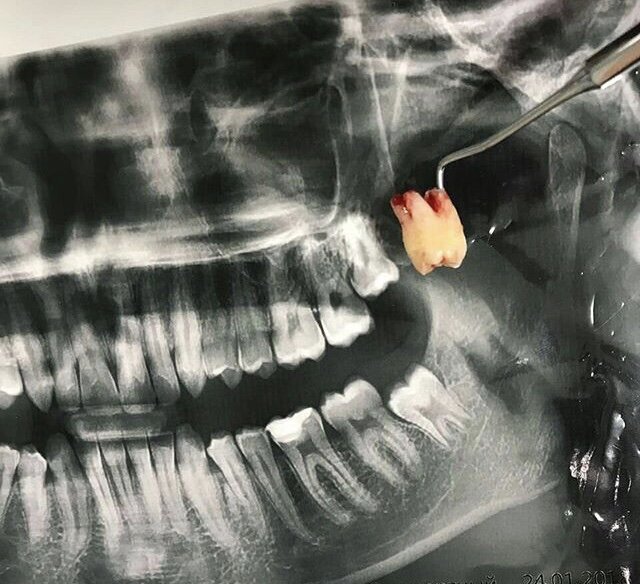

Как удаляют зуб мудрости и зачем?

По сути, показанием для удаления зуба мудрости являются любые связанные с ним неудобства, а также риск их возникновения. На красоту улыбки наличие или отсутствие восьмерки чаще всего никак не влияет, и в данном случае действительно проще ликвидировать причину, чем бороться со следствием. Функциональной нагрузки на ротовую полость зубы мудрости тоже не несут. Противопоказаний для избавления от восьмерки не так много: беременность, перенесенный недавно инфаркт, гипертония второй или третьей степени или рост зуба в зоне злокачественного образования. Удалить зуб мудрости можно и для профилактики, особенно если у пациента уже были проблемы с другими восьмерками. В муниципальных стоматологиях могут возникнуть трудности с получением направления, но частные клиники охотно возьмутся за эту процедуру.

Зуб мудрости однозначно нужно удалять в следующих случаях:

Нехватка мест в зубном ряду. В этом случае при прорезывании восьмерка будут сдвигать к центру соседние зубы, что в конечном итоге приведет к их деформации и нарушению прикуса. Кроме того, если пациенту уже показана установка брекетов, освободившееся после удаления место ускорит возвращение зубам правильного положения. Возникновение кариеса. Из-за сложного расположения восьмерки тяжело чистить, к тому же иногда они имеют поврежденную эмаль уже при прорезывании. Кариес может быстро переместиться на соседние зубы, поэтому затягивать с медицинским вмешательством в этом случае точно нельзя. Аномальное анатомическое положение в ряду. Порой зуб мудрости может расти под наклоном в сторону горла, языка или щеки. Это доставляет сильный дискомфорт и постоянно травмирует ротовую полость. Незаживающие ранки впоследствии могут привести к язвам, хронической травме слизистой щеки